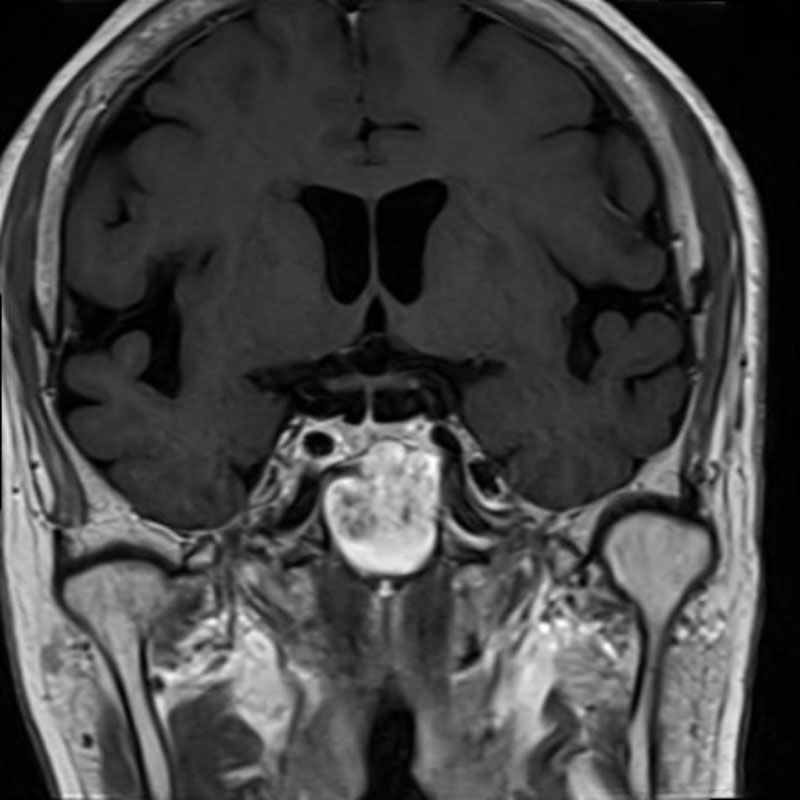

下垂体腺腫

頭蓋内腫瘍摘出術

No.’25_102 手術前1

No.’25_102 手術前2